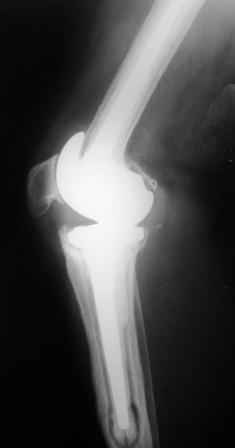

Уважаемые коллеги!Хотелось бы услышать Ваше мнение о возможности и способе помощи больной. 1939 г.р. В 1995г. эндопротезирование правого коленного сустава протезом Феникс, в 1999г. в г. Томске - ревизия - ротационный хинч W.Link. C 2005г. прогрессирует варусная деформация за счетнестабильности тибиального компонента. Попытка ортезирования - без эффекта. Попытка направить в ФСМУ без эффекта, да и больная не хочет никуда ехать.С уважением, Leonid

Технически можно надеть гвоздь на ножку протеза

Понятно что для решения на операцию артродеза необходимы веские причины. Но я не уверен что здесь асептическое расшатывание. Судя по снимкам, бедренный компонент стоит не плохо, и есть рассасывание костной ткани вокруг всего протеза в голени. Что-то мне подсказывает об инфекционном процессе, возможно вялотекущем. В наших условиях я сделал бы обследование включающее анализы крови с СОЭ, СРБ. Сделал бы пункцию коленного сустава или даже биопсию мягких тканей для посева и микроскопии.